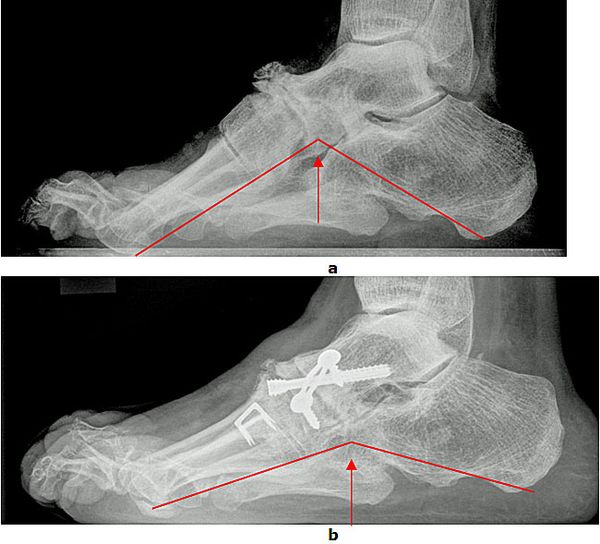

Achsanalyse durch Röntgen Belastungsaufnahmen

In der Röntgendiagnostik werden Belastungsaufnahmen des Fußes zur Bestimmung der Achsverhältnisse durchgeführt. Entscheidend ist das Verhältnis zwischen dem ersten Mittelfußknochen und dem Sprungbein sowie der Öffnungswinkel zwischen Fersenbein und Sprungbein. Die Winkel sind beim Plattfuß vergrößert. Außerdem wird der Gelenkzustand beurteilt.

Abb.3: a Absenkung des Längsgewölbes im Röntgenbild. Krankhafte Veränderung der Knochenachsen.

b Durch eine gelenkerhaltende Operationsmethode (Verlängerung des Fersenbeins (Evans Osteotomie, Calcaneus Verlängerungs Osteotomie) konnte der Fuß wieder aufgerichtet werden.